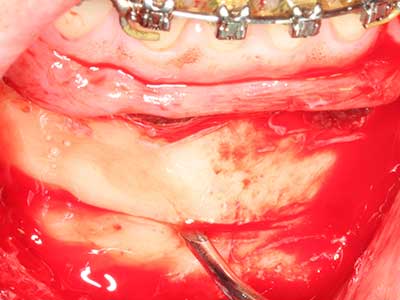

Фиг. 3: Базалното разделяне на блока е по-лесно със специалните извити накрайници.

Фиг. 4: Допълнителни автогенни костни стърготини се събират със скалер за кост.